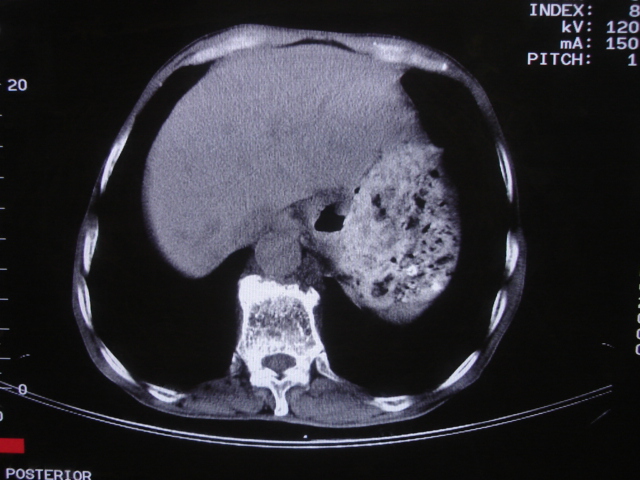

以下是引用深泽交通医院在2008-7-17 12:39:00的发言:[br]胃下垂;胃窦占位